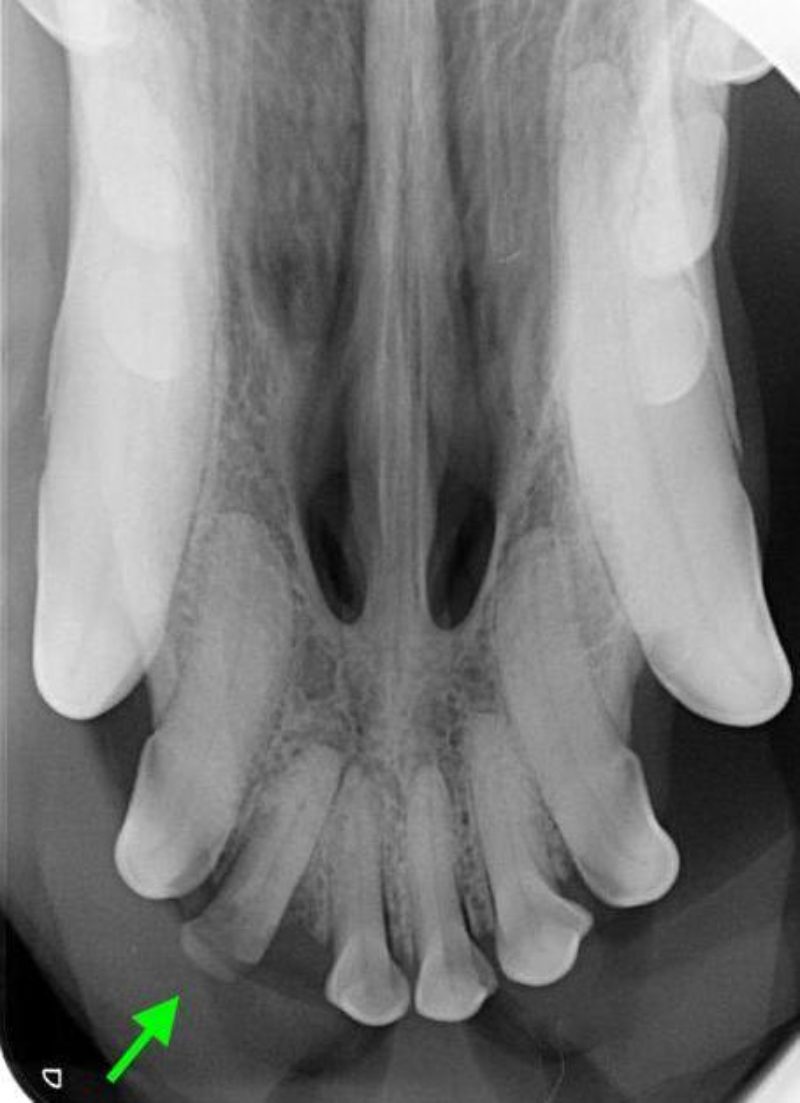

Der hübsche neun Jahre alte schwarze Mischlingsrüde Nando aus Italien wird vorgestellt, da die Besitzerin Zahnstein und einen unangenehmen Geruch aus der Maulhöhle festgestellt hat. Während der Untersuchung werden folgende Befunde erhoben: mittelgradiger Zahnstein an den meisten Zähnen, im Unter- und Oberkiefer je ein abgebrochener Schneidezahn (Abb. 1 und 2) und eine große „Zahnlücke“ im Unterkiefer rechts (Abb. 3). Hier scheinen die drei letzten Backenzähne zu fehlen. Nando ist ein sportlicher und schlanker Hund. Sein Herz schlägt regelmäßig und ohne Nebengeräusche. Dennoch untersuchen wir vor der Operation sein Blut, um mögliche Anästhesierisiken weitgehend ausschließen zu können. Wenige Tage später werden Nandos Zähne in Narkose sorgfältig von Zahnstein befreit und anschließend poliert. Von den beiden abgebrochenen Schneidezähnen und dem Bereich der vermeintlichen Zahnlücke im Unterkiefer werden Röntgenbilder angefertigt. Die Kronen der beiden Schneidezähne sind so tief abgebrochen, dass die Pulpahöhle offen liegt (Abb. 4). Im Bereich der „Zahnlücke“ zeigt das Röntgenbild Wurzelanteile nicht vollständig vorhandener oder vielleicht auch nicht vollständig ausgebildeter Zähne (Abb. 5).

Was bei augenscheinlicher Betrachtung zunächst wie eine ganz normale „Zahnlücke“ aussieht, stellt sich im Röntgenbild ganz anders dar. Bei Nando zeigt es an dieser Stelle Zahnreste, die kreuz und quer im Knochen des Unterkiefers liegen. Nun muss die Entscheidung gefällt werden, ob diese Zahnreste an Ort und Stelle belassen oder operativ entfernt werden. Wir haben die Zahnreste belassen, denn im Röntgenbild sind keine Hinweise auf eine Entzündung der Wurzelanteile oder des sie umgebenden Knochens oder die Ausbildung einer Zyste (s.u.) zu finden. Auch die äußerlich sichtbare Schleimhaut ist in diesem Bereich vollkommen reaktionslos. Nichts deutet auf die in der Tiefe des Unterkieferknochens liegenden Zahnanteile hin. Allerdings muss Nando in Zukunft weiter auf Entzündungs- oder Schmerzanzeichen überwacht werden, denn die Situation könnte sich im Verlaufe seines Lebens noch ändern. Mit zunehmendem Alter wird das jedoch immer unwahrscheinlicher. Eine regelmäßige Röntgenkontrolle zur Evaluierung der tiefliegenden Wurzelanteile ist wünschenswert.

So waren bei Nando sowohl das Alter von neun Jahren als auch die fehlenden klinischen und radiologischen Anzeichen für eine Entzündung bzw. Knochenzyste ausschlaggebend für die Entscheidung, die Wurzelteile an Ort und Stelle zu belassen. Hätten die Röntgenbilder gezeigt, dass sich eine Knochenzyste im Bereich der Wurzelteile ausgebildet hätte, wäre eine operative Entfernung der Zyste und der Wurzelanteile notwendig gewesen. Nando hatte jedoch Glück, ein solch aufwändiger Eingriff war bei ihm nicht notwendig. Er konnte kurze Zeit nach dem Eingriff, von Zahnstein und zwei abgebrochenen Zähnen befreit, wieder nach Hause gehen. Es ist sichergestellt, dass er keine Zahnschmerzen hat und in seiner Maulhöhle keine Voraussetzung für die Entwicklung einer Parodontitis mehr gegeben ist. Wenn die Besitzer seine Zähne täglich bürsten, können sie diesen Status erhalten und gleichzeitig die vermeintliche Zahnlücke im Blick behalten.